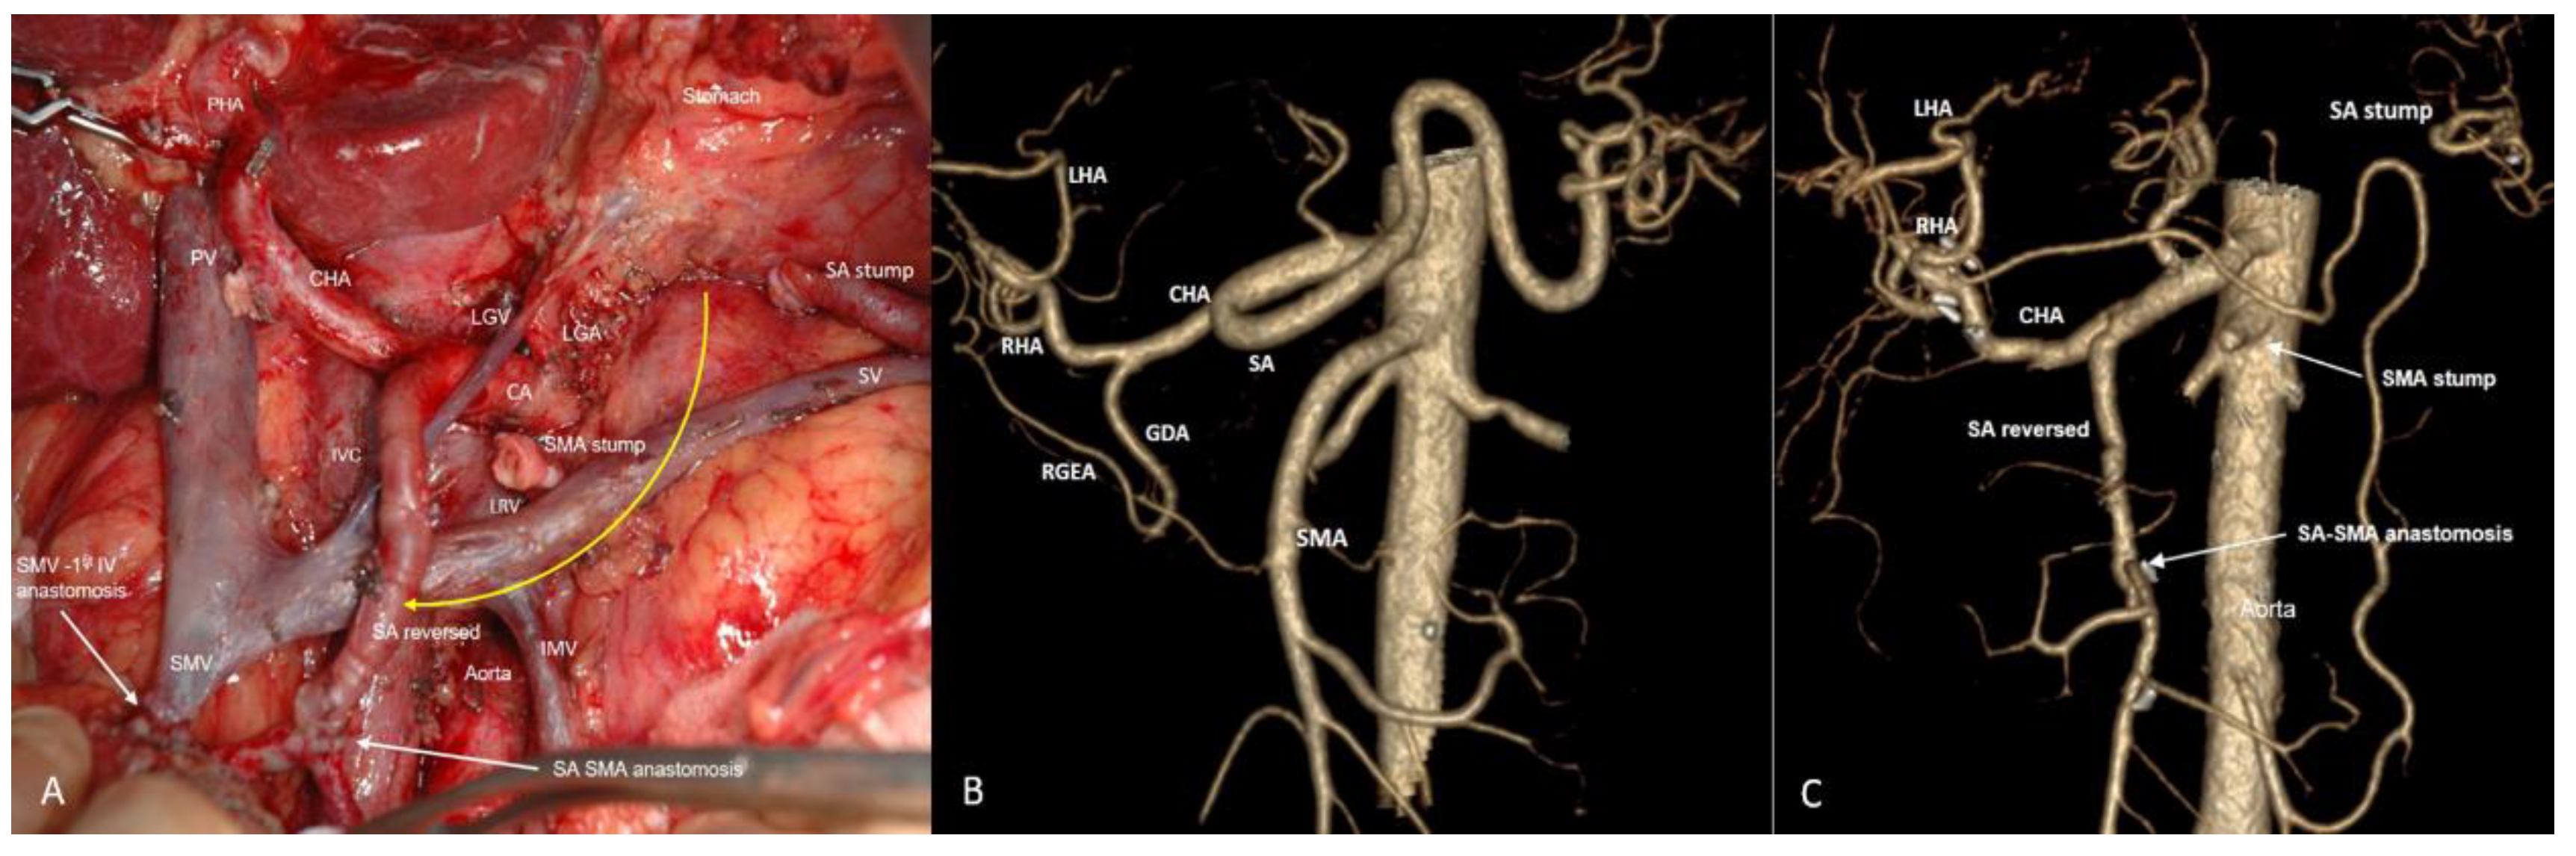

3.4. Spleen-Preserving Pancreatectomies with Resection of the Splenic Artery (Vessels) for Border Line Resectable and Locally Advanced Pancreatic Head Cancers